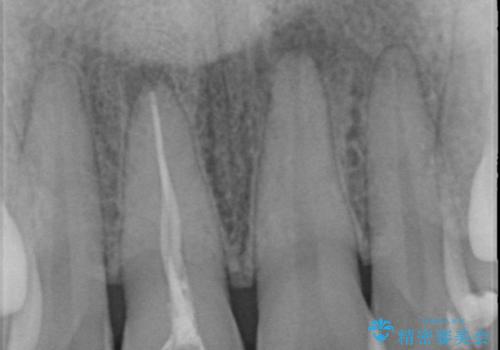

X線検査を行ったところ、共に深い虫歯が原因となり神経が死んでしまっている状態であることがわかり、根管治療を行ったのちセラミック補綴を行っていくこととなりました。

最終的なセラミッククラウンの精度・色調は非常に大事ですが、そこに至るまでの根管内環境の洗浄、ファイバーコアによる緊密な封鎖も長期的な予後に重要であると考えます。